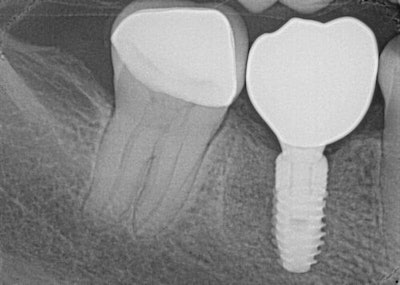

A final radiograph (Figure 14) confirmed ideal seating, emergence profile, and a harmonious relationship with adjacent structures, completing the entire process in a single patient visit.

Figure 14: Final radiograph showing seated restoration.